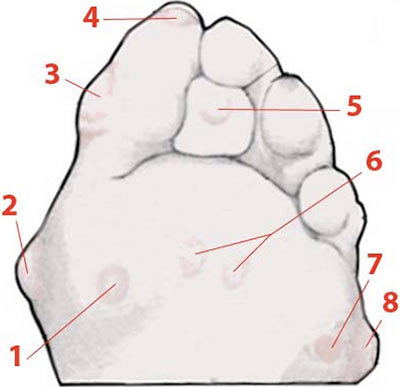

1. Durillon, 2. oignon, 3. Durillon, 4. Cor sous l’ongle,

5. Cor, 6. Durillons sous les têtes de métatarsiens,

7. Durillon, 8. Oignon.

Comme le cor et l’œil de perdrix, le durillon est issu d’une hyperkératose de localisation précise : on le trouve face plantaire, en dessous des têtes métatarsiennes.

Un défaut statique du pied au niveau des métatarsiens va favoriser l’émergence d’un durillon. La pratique de la danse sur un revêtement trop dut et la répétition de réceptions de sauts sont aussi des circonstances fréquentes d’apparition des durillons.

Cela se présente sous la forme d’une petite tuméfaction, une plaque de kératose assez étendue, compacte, plus ou moins douloureuse sous une tête métatarsienne, d’un diamètre souvent légèrement supérieur à celui du cor. Il est toujours situé au niveau d’une zone d’appui important. Il se développe plus en largeur qu’en profondeur. Il est mobile avec la peau et n’adhère pas au tissu sous-jacent.